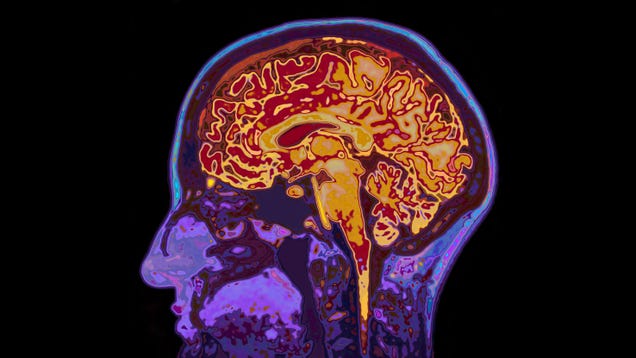

An experimental drug for Alzheimer’s disease appears to have shown successful results in a major large-scale clinical trial. The drug’s makers announced Tuesday that their treatment slowed down people’s rate of cognitive decline in a Phase III trial. The findings will likely pave the way for the drug’s approval in the…

Source: Gizmodo – Experimental Alzheimer’s Drug Succeeds in Large Trial, but Questions Remain